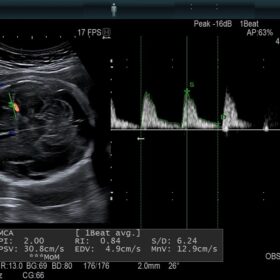

Women’s Health

Be equipped for breast pathologies and fetal assessment.

- Highly sensitive colour mode to replace contrast agents

- Doppler measurements from two gates in same heart cycle

- Advanced vessel and blood flow analysis tools